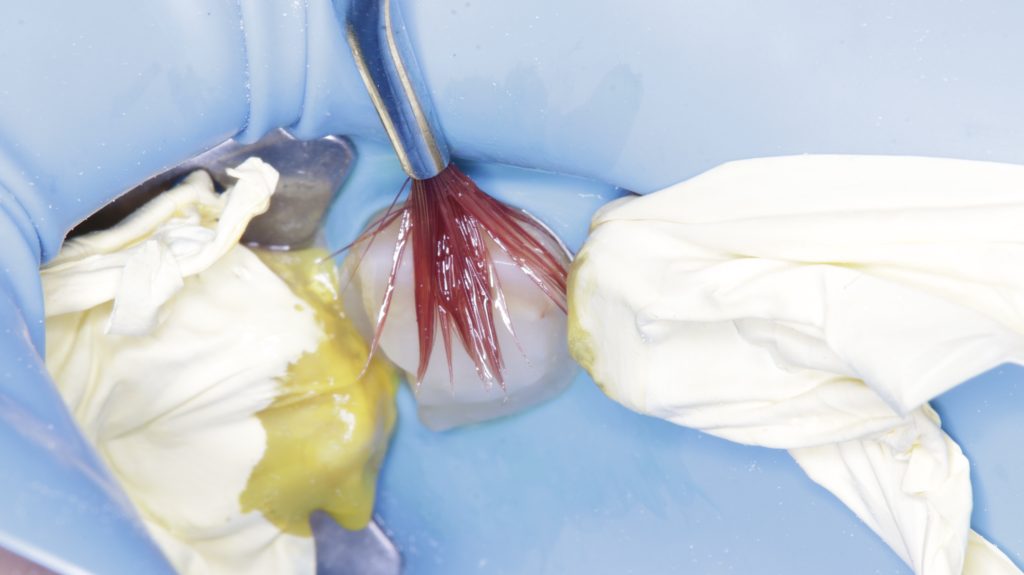

In this picture shaw the margin very deep lingually

After cleaning and rubber-dam isolation and additional clamp to secure the dam and to exposed margin lingually

Contact open to Applicant band

Teflon backing to secure selling lingually